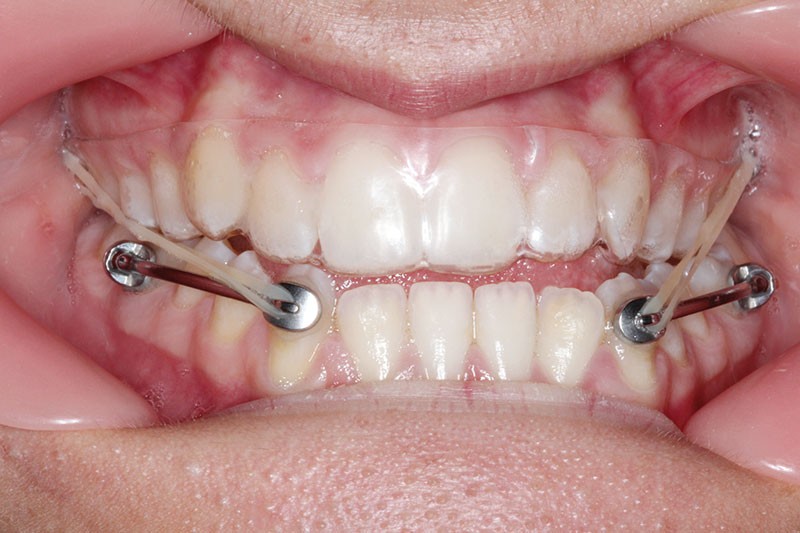

1re phase : recul des secteurs latéraux mandibulaires avec le Motion Classe III Carriere (fig. 4 à 6)

Nous mettons en place des bras latéraux Motion associés à des élastiques intermaxillaires ancrés sur des brackets sur 17 et 27 et une gouttière thermoformée maxillaire portée jour et nuit :

• 1er mois : élastiques 6 oz. 1/4”

• 2e mois et suivants : élastiques 6 oz.1/4“

L’objectif de cette étape est d’obtenir un recul des secteurs latéraux mandibulaires afin de positionner les molaires et canines en classe I et de réorienter le plan d’occlusion en haut en avant.